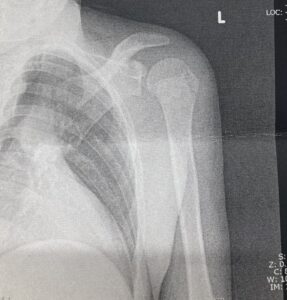

2枚目の写真は健側。正常な骨です。